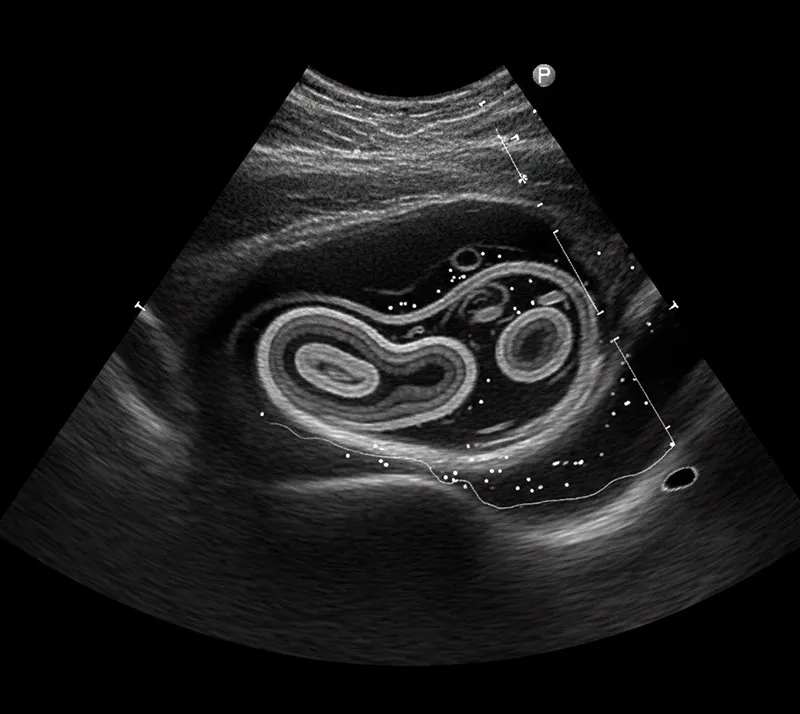

سونوگرافی روده، یک روش تصویربرداری غیر تهاجمی و بدون درد برای پایش بیماری های التهابی روده (IBD) می باشد که از امواج صوتی برای ایجاد تصاویر دقیق و واضح از روده کوچک و بزرگ استفاده می کند.

در این روش، امواج صوتی از روده منعکس شده و تصاویر روشنی ایجاد می کنند که ضخامت دیواره روده (ضخیم شدن دیواره می تواند نشان دهنده التهاب باشد) و جریان خون (افزایش جریان خون می تواند نشان دهنده التهاب باشد) را نشان می دهد.

سونوگرافی روده شبیه همان سونوگرافی بارداری است. برای شروع این فرایند، ژل مخصوصی روی شکم شما قرار داده می شود و سپس پروب را روی ناحیه مورد نظر حرکت می دهند تا تصاویر زنده و واقعی از روده های شما ثبت شود.

شما می توانید این تصاویر را هم زمان روی صفحه نمایش مشاهده کنید و معمولاً فرآیند بین ۱۰ دقیقه تا نیم ساعت طول می کشد.